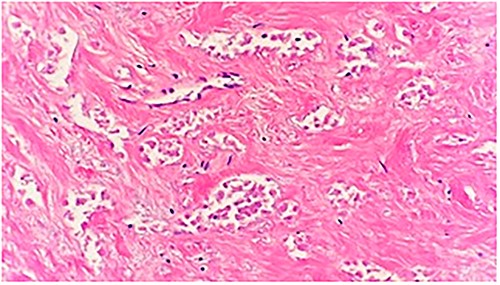

An 84-year-old female presented to the breast surgery office for biopsy proven malignant 2-cm palpable mass on physical examination in the right retroareolar region. Her medical history was significant for hypertension, diabetes mellitus, and stroke. She had a diagnostic bilateral mammogram and sonogram along with a biopsy of the site in question, at another outside facility, which had yielded invasive ductal carcinoma with perineural invasion. In addition, indeterminate linear microcalcifications were visualized in the central right breast 3-cm posterior to the mass and also in the central far posterior lower right breast. These warranted another diagnostic mammogram and sonogram. Repeat diagnostic mammogram and sonogram were remarkable for: biopsy-proven malignant 1.2-cm mass in the right retroareolar region. Additional suspicious microcalcifications 3- and 7-cm posterior to the mass were noted, classified as BIRADS 4. She underwent a stereotactic biopsy. Pathology for the retroareolar mass was positive for moderately differentiated invasive ductal carcinoma with perineural invasion and pathology for calcifications was positive for Ductal Carcinoma in Situ (Fig. 1). Invasive ductal carcinoma was positive for ER (95%), PR (50%), and negative for Her-2/Neu. Ductal Carcinoma In Situ was positive for ER (90%–95%) and negative for PR (0%). Subsequently, upon an extensive discussion with the various options including but not limited to lumpectomy and mastectomy, she elected to undergo a right simple mastectomy without reconstruction with right axillary sentinel node biopsy. Surgical pathology was remarkable for no evidence of active malignancy in any of the previously biopsied areas; evidence of nodular necrosis of tumor cells noted (Fig. 2) consistent with inflammatory reaction and fibrocystic changes. Patient was started on Anastrozole and the following postoperative course was unremarkable.

Microscopic examination shows a sheet of nonviable tumor cells with necrosis. H&E 20×.